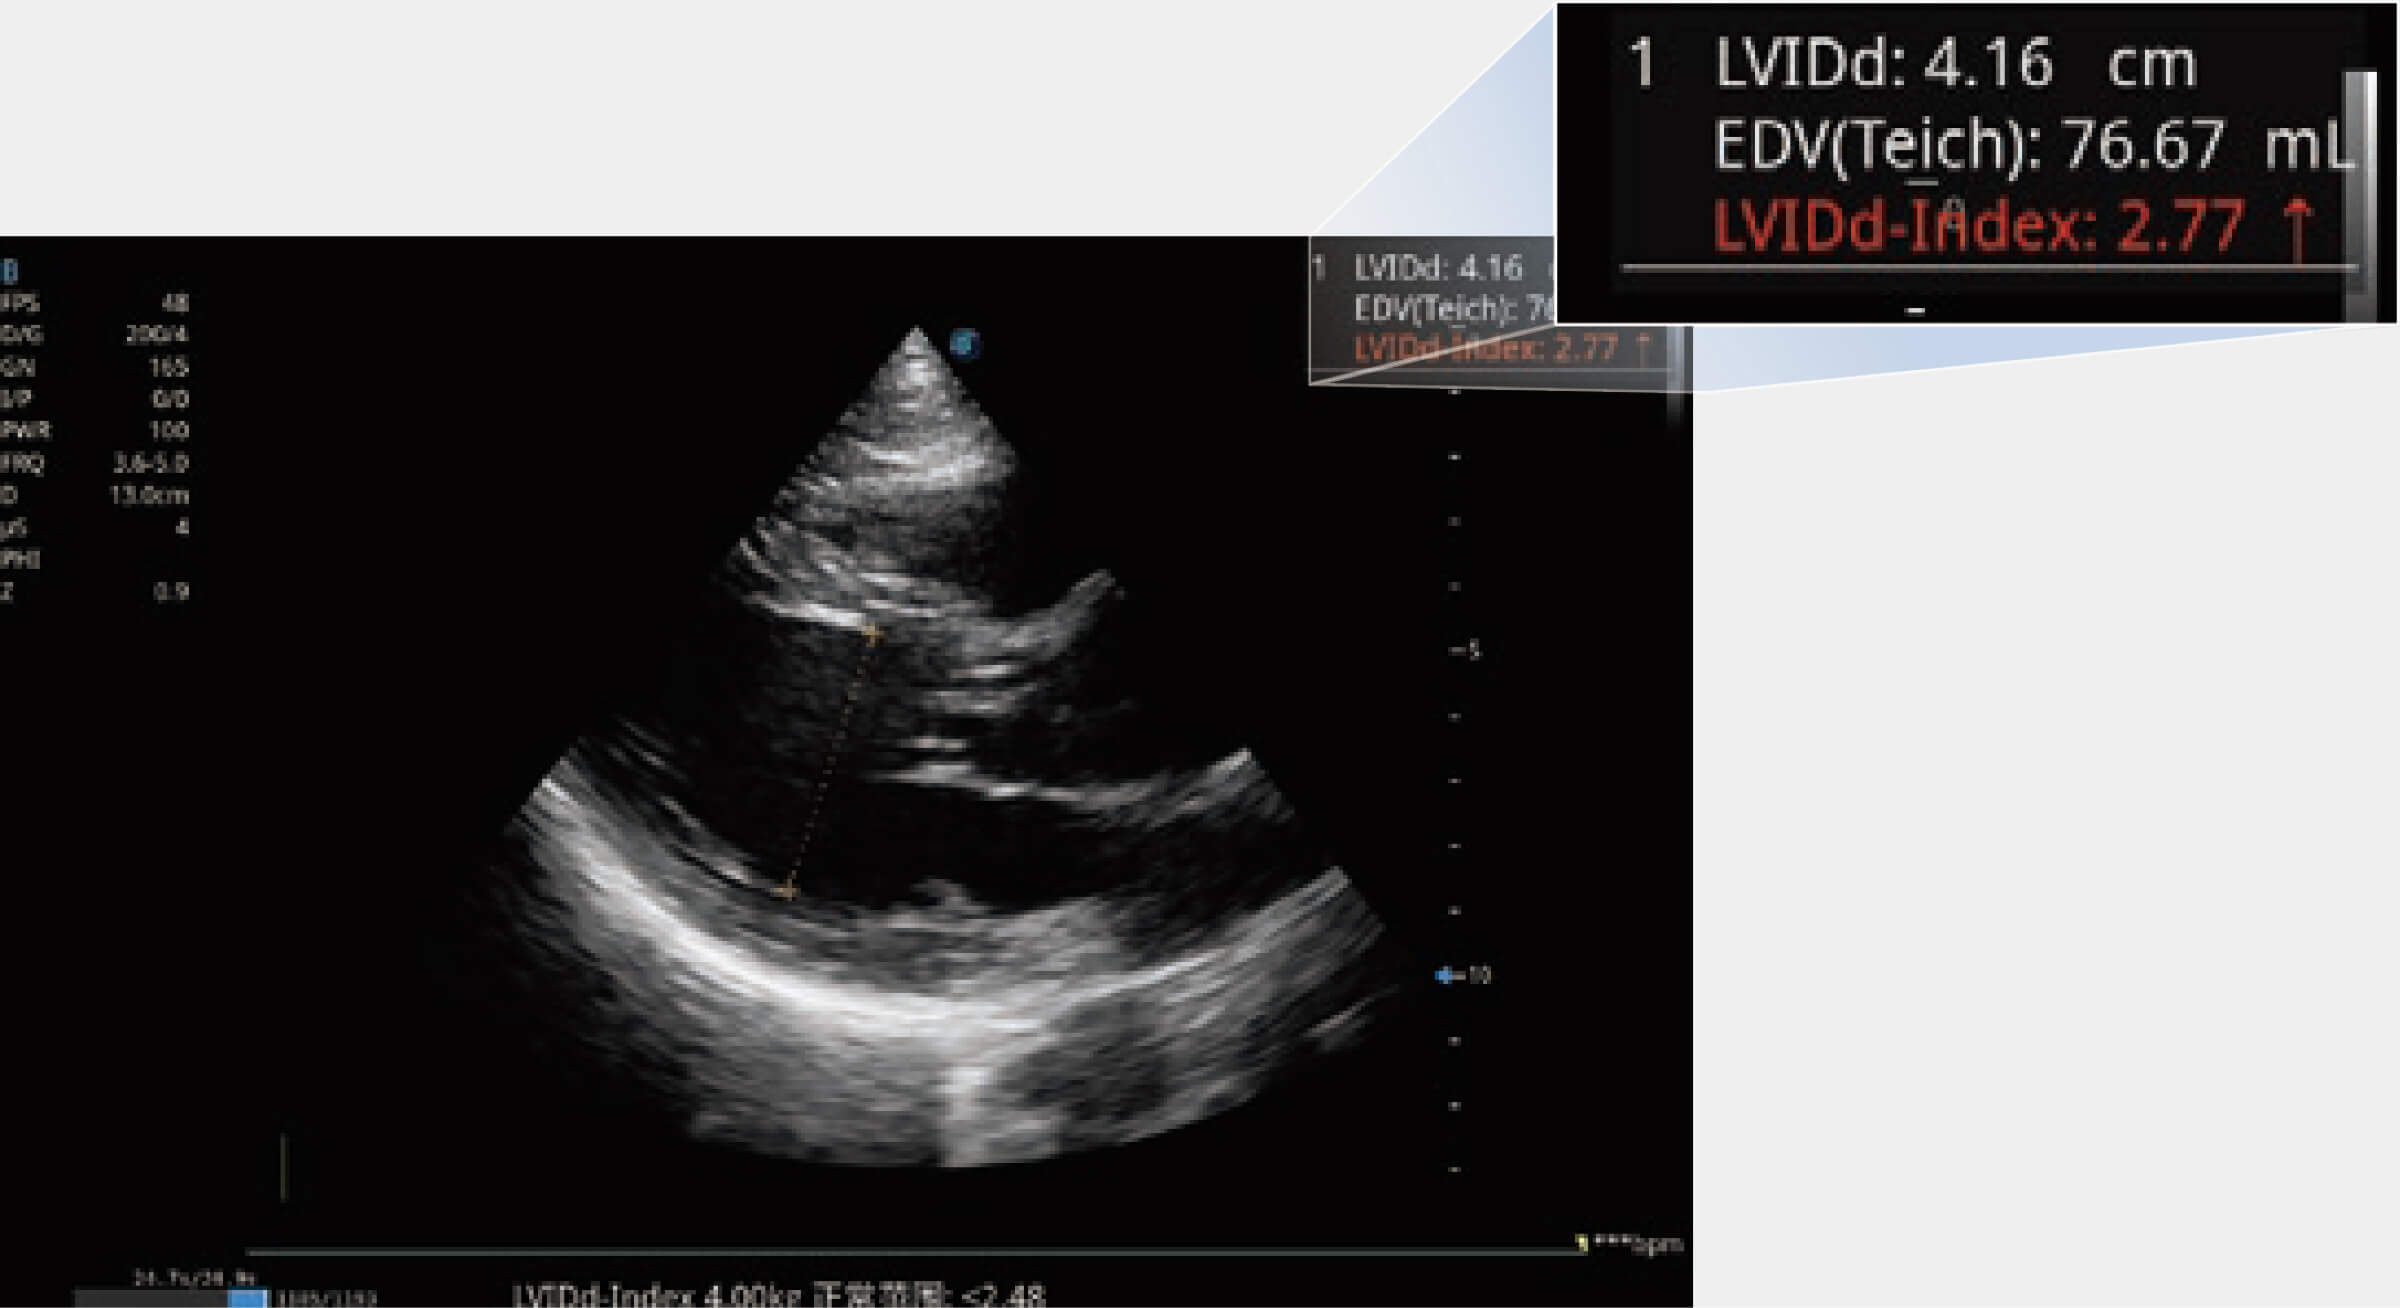

當(dāng)心臟測(cè)量結(jié)果超出正常范圍時(shí),可實(shí)時(shí)預(yù)警提示動(dòng)物醫(yī)生,減少疾病漏診概率。

為精細(xì)結(jié)構(gòu)及組織邊緣提供高清晰度的圖像和更大的成像視野。幫助減輕醫(yī)生的用眼疲勞,快速精準(zhǔn)獲得測(cè)量的數(shù)據(jù)。